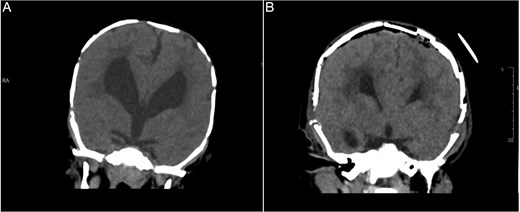

An 11-month-old female infant, born to unrelated Saudi parents, was referred to our facility with unilateral left coronal craniosynostosis, congenital microcephaly, global developmental delay, and a confirmed ZIC1 gene mutation. Comorbidities included a patent foramen ovale, aortopulmonary collateral vessel, G6PD deficiency, and gastroesophageal reflux disease (GERD). At birth head circumference was 29 cm (<first percentile), and progressive skull asymmetry and squinting were noted over time. Developmentally, she exhibited delayed gross and fine motor skills with limited object transfer. On examination, she was alert and visually tracking, with inward ocular deviation (esotropia). Head circumference was 37 cm (<first percentile) with anterior plagiocephaly and towering of the left frontal region (Fig. 1). Pupils were equal and reactive. Fundoscopy and cranial nerve examinations were unremarkable. Gross motor power was within normal limits, except for moderate lower limb spasticity. 3D reconstruction computed tomography (CT) confirmed premature fusion of the left coronal suture with subtle elevation of the superolateral orbital rim, indicating harlequin sign (Fig. 1). Brain CT showed corpus callosum agenesis, colpocephaly, mild ventriculomegaly, right cerebellar and pontine hypoplasia, and a large cisterna magna, consistent with the reported ZIC1-related malformation spectrum (Fig. 2). Given the progressive deformity and concerns of increased intracranial pressure that might be partially contributing to her neurodevelopmental delay, anterior cranial vault expansion with fronto-orbital advancement was performed jointly by the neurosurgery and plastic craniofacial teams (Fig. 3). Intraoperatively, left-sided dural tension was appreciated, indicating localized increased intracranial pressure. The orbital bandeau was reshaped and advanced, achieving immediate cosmetic improvement (Fig. 4). The patient tolerated the surgery well and recovered uneventfully. At her 4-month follow-up, she showed developmental progress including standing without support, purposeful hand use, and verbalization (“Baba”). At 6-month follow-up, brain CT revealed areas of bone resorption which led to the placement of a ventriculo-peritoneal shunt (Fig. 5). The known association of ZIC1 mutation with tethering of the cord prompted spinal magnetic resonance imaging (MRI) screening. Positive findings indicated an untethering procedure, which was successfully done (Fig. 6).

Brain CT showing: A-corpus callosum agenesis, B-colpocephaly, C-mild ventriculomegaly, D-right cerebellar and E-pontine hypoplasia, F-large cisterna magna.

Brain CT bone window illustrating ventriculomegaly and bone resorption at six-month follow-up (A), compared to immediate post operative image (B).